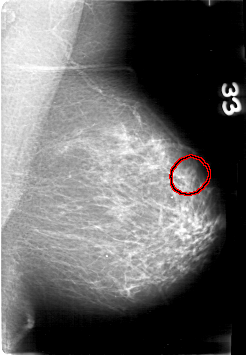

D_4089_1.RIGHT_MLO

FILE: D_4089_1.LEFT_CC.OVERLAY

TOTAL_ABNORMALITIES 1

ABNORMALITY 1

LESION_TYPE MASS SHAPE OVAL MARGINS OBSCURED

ASSESSMENT 0

SUBTLETY 3

PATHOLOGY BENIGN

TOTAL_OUTLINES 1

BOUNDARY